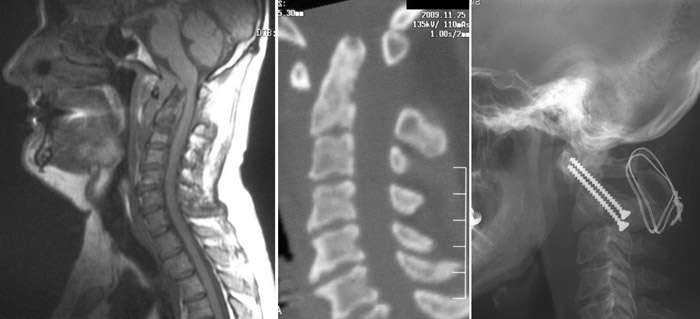

- Рентгенография. Медработники обычно проводят это исследование всем пострадавшим от травмы, у кого есть подозрение на повреждение спинного мозга. Рентген может выявить проблемы с позвонками, опухоли, переломы или дегенеративные изменения в позвоночнике.

- Компьютерная томография (КТ). КТ может предоставить лучшее изображение патологии, видимой на рентгеновских снимках. Этот вид обследования использует компьютер, чтобы воссоздать серию изображений поперечного сечения, которые могут выявить проблемы, связанные с костями, дисками и другие проблемы

- Магнитно-резонансная томография (МРТ). МРТ использует магнитную силу и радиоволны, чтобы воспроизвести изображения, полученные через компьютер. Этот тест очень помогает в ситуациях, когда необходимо рассмотреть спинной мозг и выявить грыжу межпозвоночного диска, сгустки крови и другие образования, которые могут сдавливать спинной мозг. Но МРТ нельзя проводить пациентам с сердечными водителями ритма или пострадавшим, которым необходима аппаратура, поддерживающая жизнедеятельность организма или приспособление для вытягивания шейного отдела позвоночника.

Цель операции – стабилизация позвоночника металлическими конструкциями (имплантантами). Наша клиника была первой в СНГ, кто применил современные конструкции при переломах позвоночника. Сейчас мы используем импортные конструкции типа CD Horison Legacy (США), Atlantis (США), Sextant (США), Socore (Франция). Операции требуют сложной рентгеновской техники и специального инструментария. При неосложненных переломах позвоночника больные могут ходить после таких операций уже на второй - третий день после операции. Также в Международном центре нейрохирургии впервые в Украине был внедрен метод миниинвазивных операций при переломах позвоночника.